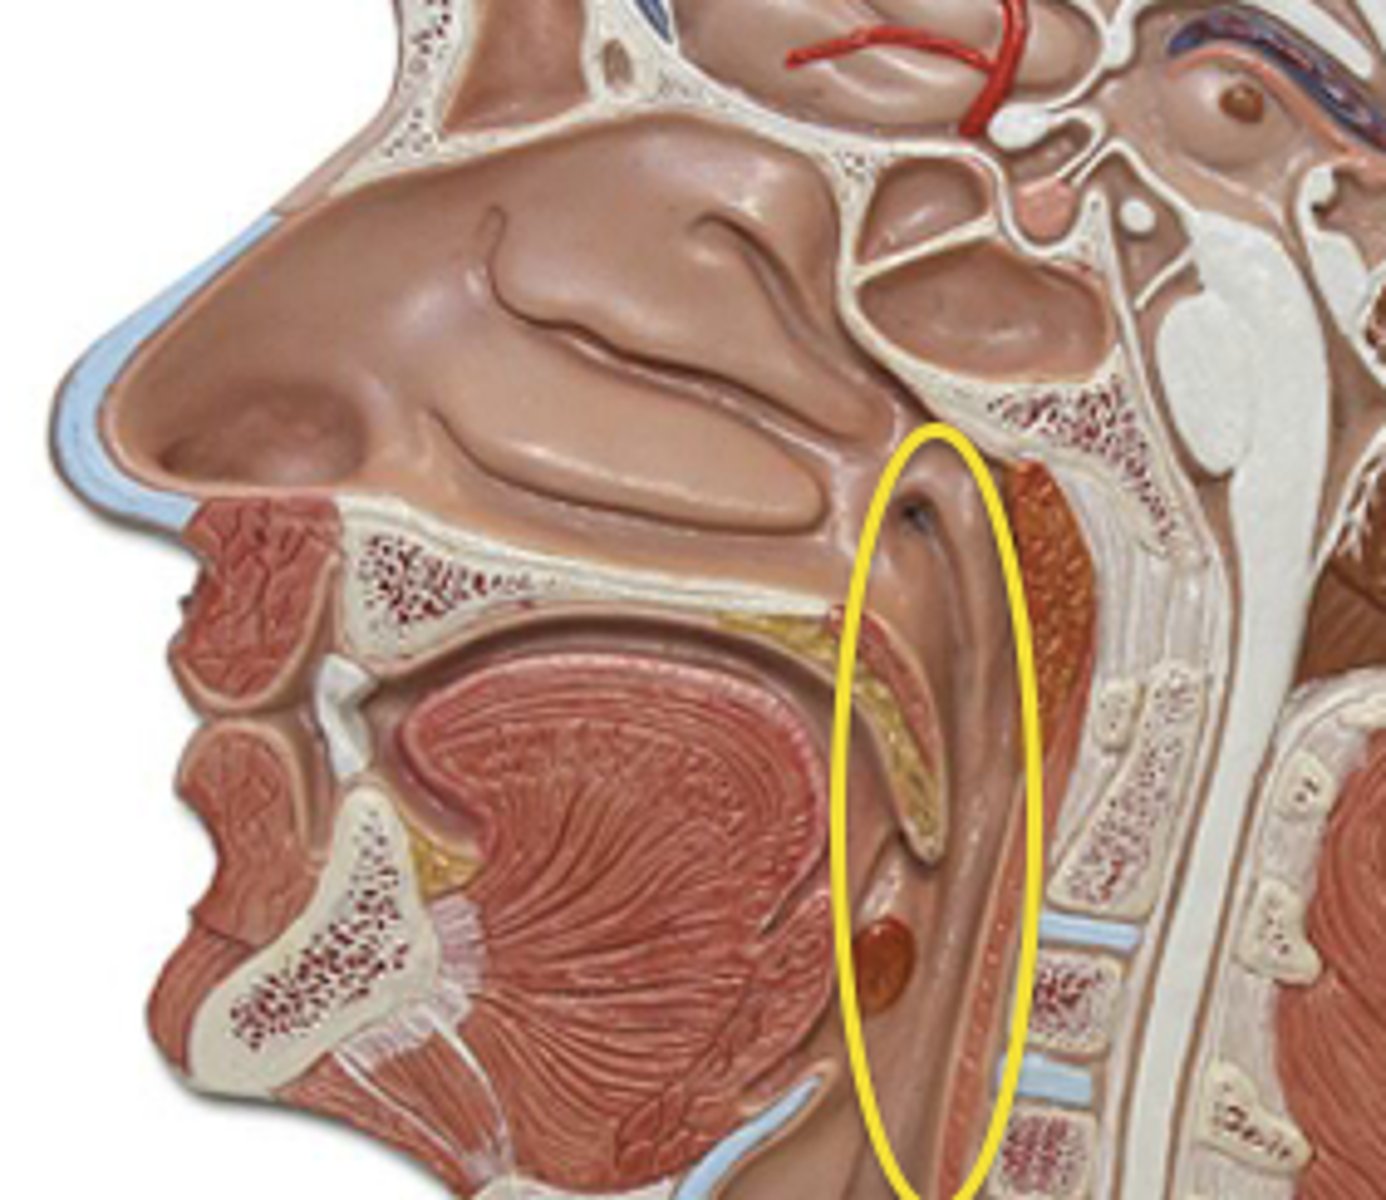

Pharynx

An oval tube, larger side to side then front to back

Connective tissue

predominates at the top;

muscle predominates at

the bottom

Continuous with

esophagus at lower end

Pharynx

Three cavities

Lower boundaries are level of hard palate

(nasopharynx), hyoid bone

(oropharynx), and base of

the cricoid cartilage

(laryngopharynx)

Nasopharynx contains the

auditory tubes and

nasopharyngeal tonsils

(adenoids)

Pharynx

Opening of oropharynx is

through the faucial isthmus

(bounded by anterior

faucial pillars)

Oropharynx contains the

palatine tonsils and lingual

tonsil

Pharynx

Pharyngeal tube has 3 layers

- Fibrous layer (aponeurosis)—predominately in upper part of pharynx

- Muscular layer

- Mucous layer

Aponeurosis attached to base of skull anterior to foramen magnum

- Pharyngeal muscles attached to this aponeurosis

3 pairs of muscles, referred to as constrictors

Action of each is to reduce the diameter of a portion of the pharyngeal cavity